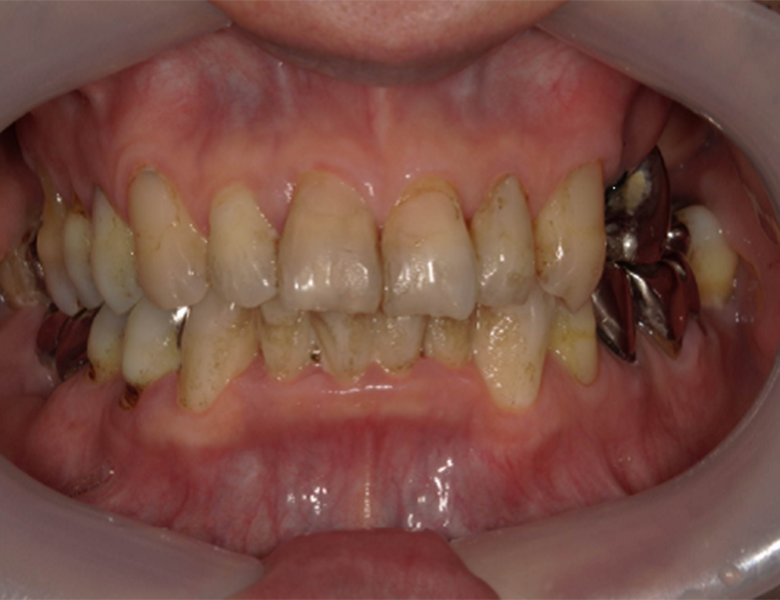

治療前

武蔵中原の歯医者、中林デンタルケアークリニックの予防症例、治療前

カウンセリング・診断結果 拝見したところ、全体に薄い色のステインと歯と歯ぐきの境目には、細菌の塊である「歯垢」と、歯垢が唾液などで固まった「歯石」が付着していました。

これらは、歯を支える骨や歯の周りの組織が徐々に破壊される「歯周病」の症状です。

虫歯や被せ物の治療の前に、歯ぐきの炎症を取り除くための歯周病治療が必要です。